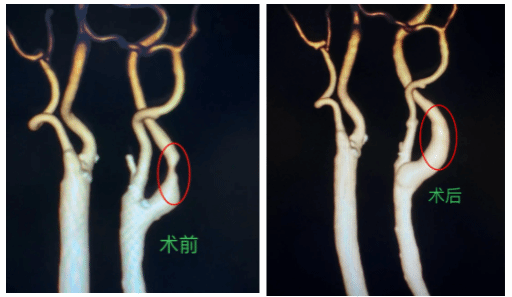

据悉,这名患者1年前频繁出现头晕、左侧肢体乏力的症状,近一周这些症状显著加重,他随即到河池市人民医院神经外科就诊。经颈部血管CTA检查发现,患者左侧颈内动脉存在重度狭窄,狭窄率高达85%,原本应通畅的血管管腔如今仅剩“细线样”通道,情况十分危急。

手术当天,手术团队在30分钟血流阻断极限窗口期内,精准控制每个毫米级的操作,为患者成功实施颈动脉内膜剥脱术,剥离出2.5cm黄色脂质性斑块。次日,患者头晕症状消失,左下肢肌力从Ⅲ级恢复至Ⅳ级,血管造影显示管腔通畅。“现在感觉特别清爽,走路也有劲了!多亏了医护团队的精湛医术,让我重获健康!”患者出院时自述状态变好。